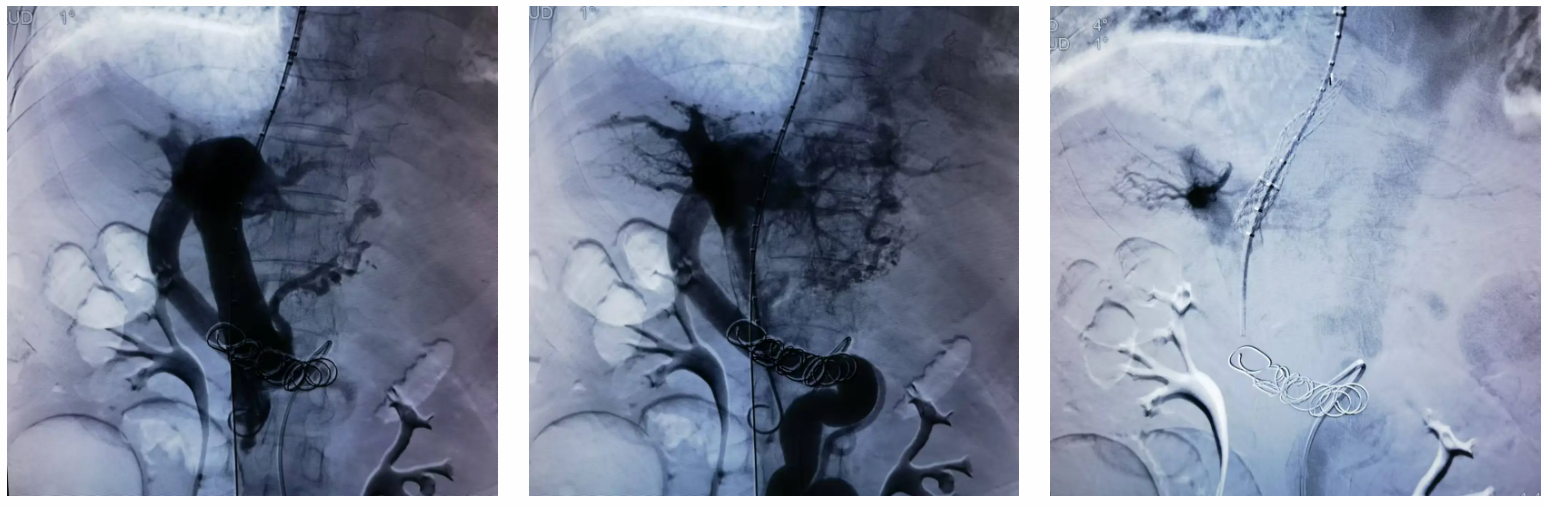

完善术前准备后,外周介入团队在上级专家指导下为该患者实施了 TIPS 手术。手术过程包括了穿刺、造影、HVPG 测压、球囊扩张、支架植入、血管栓塞等多项技术操作,成功在肝静脉、门静脉之间建立通道,植入专用支架维持长期通畅性,降低门静脉高压。术后,患者恢复良好,手术效果显著。